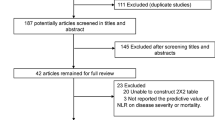

Literature search and study selection

Fig. 3 shows the work flow of the citations reviewed and the studies included. Our search strategy yielded 327 citations after de-duplication, and 35 potential citations were full-text reviewed. Finally, 16 citations were included. The study from Yabing Guo and Wenhua Liang reported 2 sets of data. Therefore, 19 datasets were included in the quantitative synthesis (18 datasets from 16 studies combined with our case-control study) [6, 20,21,22,23,24,25,26,27,28,29,30,31,32,33,34].